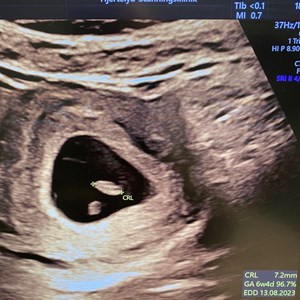

Bare 11 dage mellem de 2 billeder ! Fantastisk hvilket potentiale der er i sammensmeltnin...

Skal du til tidlig scanning i graviditetens første trimester ?? Der er meget stor forskel...

TIDLIG SCANNING - hvorfor er det en god idé ? En tidlig scanning giver jer først og fremm...